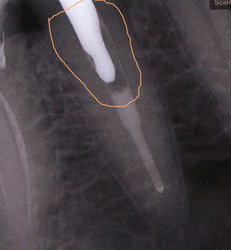

У меня в зубе был пульпит, его вылечили, но спустя время он снова образовался. Пошла к врачу, попала на новогодние праздники, к сожалению, вытащили старую пломбу, и заложили мышьяк. Когда отошла заморозка боль стала сильной. Приняла Нимесил, но боль не утихла. С трудом уснула, а когда проснулась, то у меня онемела правая часть лица (губа, подбородок, щека). Уже 3 дня не проходит онемение, челюсть вся болит, передние зубы не чувствую, но они тянут. Сегодня сходила, сделала снимок. Сказали, что надо вылечить 2 зуба, пошло воспаление. Меня волнует больше онемение.

Без клинического осмотра сложно определить однозначно причину. Похоже, в области пролеченного зуба имеется периапикальное воспаление. В области дистального корня соседнего зуба, также определяется разрежение костной ткани. Исходя из снимка, сложно судить, так как возможно наличие артефактов. Причиной онемения может быть воспалительный процесс в области нервных окончаний.